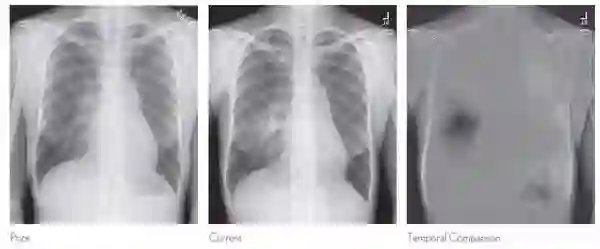

在医疗领域,尤其是皮肤病检测,图像识别也很重要。用户可以拍摄照片,获得初步诊断。斯坦福大学的研究人员开发了可以发现皮肤癌的算法。根据结果,其诊断皮肤癌的效率与专业医生相当。该算法并未投入生产,仍有商业机会。我们也期待医疗保健app的出现,特别是x射线诊断和超声诊断,以及可以通过图片诊断糖尿病患者不能吃哪些食物。微软、谷歌、亚马逊提供的云服务消除了开发人员将计算机视觉应用生产的障碍。